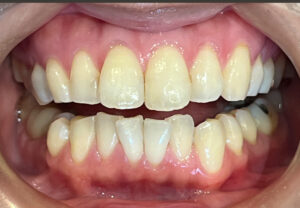

今回は、前歯のレイヤリングジルコニアセラミックの

治療をされた患者さまのご紹介です!

歯周治療、虫歯治療、審美治療の総合的な治療をおこないました。

修復の材料はほぼジルコニアセラミッククラウンで統一しています。

天然の歯は事前にホワイトニングを行い、全体的にトーンアップさせて、

それに合わせてカラーを決めています。

前歯のレイヤリングジルコニアはセラミストのデジタルトライインを行って

作製します!

全体的に綺麗になって患者さまもとても喜んでおられました♪